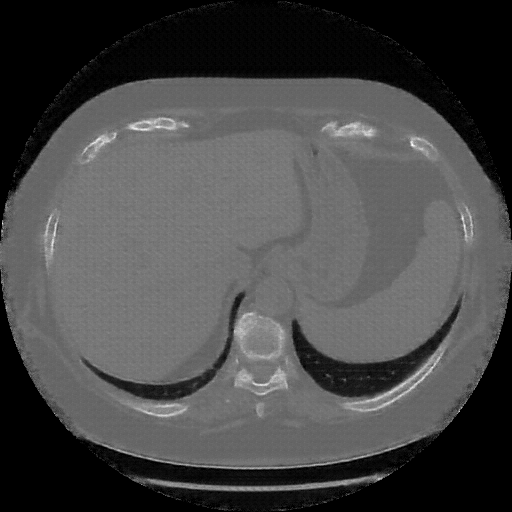

Reconstructed NATIVE CT scan (cycle consistency)

Full window (WL 1023.5, WW 4095 β†’ Low βˆ’1024, High +3071)

Actual HU range: [-1024.0, 1214.3]

Lung window (WL -600, WW 1500 β†’ Low βˆ’1350, High +150)

Actual HU range: [-1350.0, 150.0]

Mediastinum window (WL 40, WW 400 β†’ Low βˆ’160, High +240)

Actual HU range: [-160.0, 240.0]